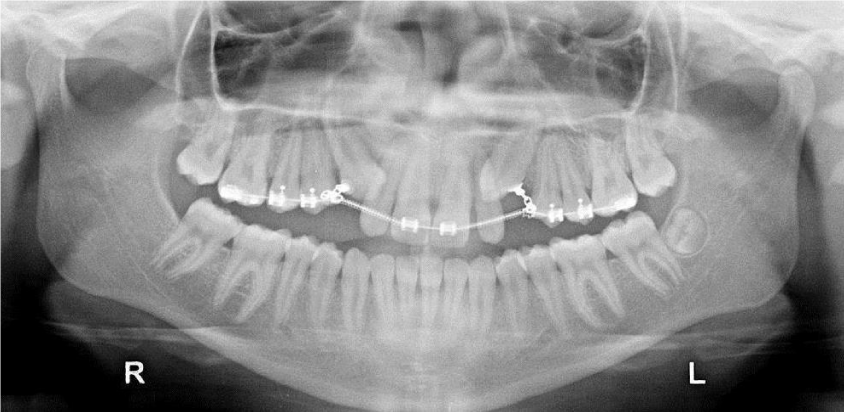

After a week the suture and the surgical dressing were removed, and light orthodontic force (no more 60 grams/2 ounces) with elastic ligatures was started. Concurrently sufficient space was created in the arch thus reducing the diastema. A preformed round arch wire 0.020 was used to provide sufficient stiffness (Figure 2b-c).

During the treatment two end oral radiographs were made on each side to ensure that the movement of canine was not damaging the roots of the neighboring teeth. When the crowns were erupted a metallic canine bracket was bonded, and the remaining movements were made with sectional, later repositioning the bracket twice. A Flexiloy tm 0.021 X 0.025 was the finishing arch and an Essix retainer was used for retention. The active treatment lasted 2 years long. Both the canines at the end of treatment had good periodontal conditions (Figure 2d, 3a-c).